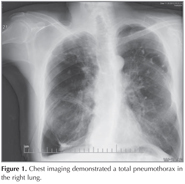

63-year-old male patient applied to emergency clinic with acute-onset dyspnea and substernal chest pain. He had a history of 60 pack-year smoking and ten years before that, he had been first told that he had emphysema and was treated with inhaled bronchodilators. Because of worsening dyspnea, he was treated with bullectomy five years ago. He had been admitted to the hospital for three times with a similar presentation; a spontaneous, right basal pneumothorax and was treated with tube thoracostomy. He was conscious, with vital signs of arterial blood pressure 135/80 mmHg, the heart rate 92 beats per minute, respiratory rate 28 per minute and an oxygen saturation of 89% at room air. There were decreased respiratory sounds in all zones on the right lung auscultation. Chest imaging demonstrated a total pneumothorax in the right lung (Figure 1). On thoracic-computed tomography (CT), bullous areas at the apexes of both lungs and a right pneumothorax were observed (Figure 2). Tube thoracostomy was performed. Although he had clinically improved, there was no improvement of the right pneumothorax, therefore surgery was considered. But this was contraindicated because of his healthy status. Because of prolonged chest drainage causes prolonged hospital stay and many complications; he discharged with drain tube connected to a Heimlich valve. Two weeks after hospital discharge until the patient could tolerate the drain being clamped, negative aspiration and talc pleurodesis were performed twice without satisfactory results. Based on a published report, endobronchial valve was attempted. Baloon catheter was inserted via the working channel of the flexible bronchoscope and balloon inflated on the right upper lobe. With occlusion of the right upper lobe bronchus, the air leak was ceased. 3 Zephyr valve were (4 mm diameter valve in apical and posterior segments, 5.5 mm diameter valve in anterior segment) placed to stop the air leak (Figure 2). After the procedure his health status was improved, he was decanulated and discharged within 1 week. On 7-month follow up, complete expansion of the lung was detected and no pneumothorax was observed.